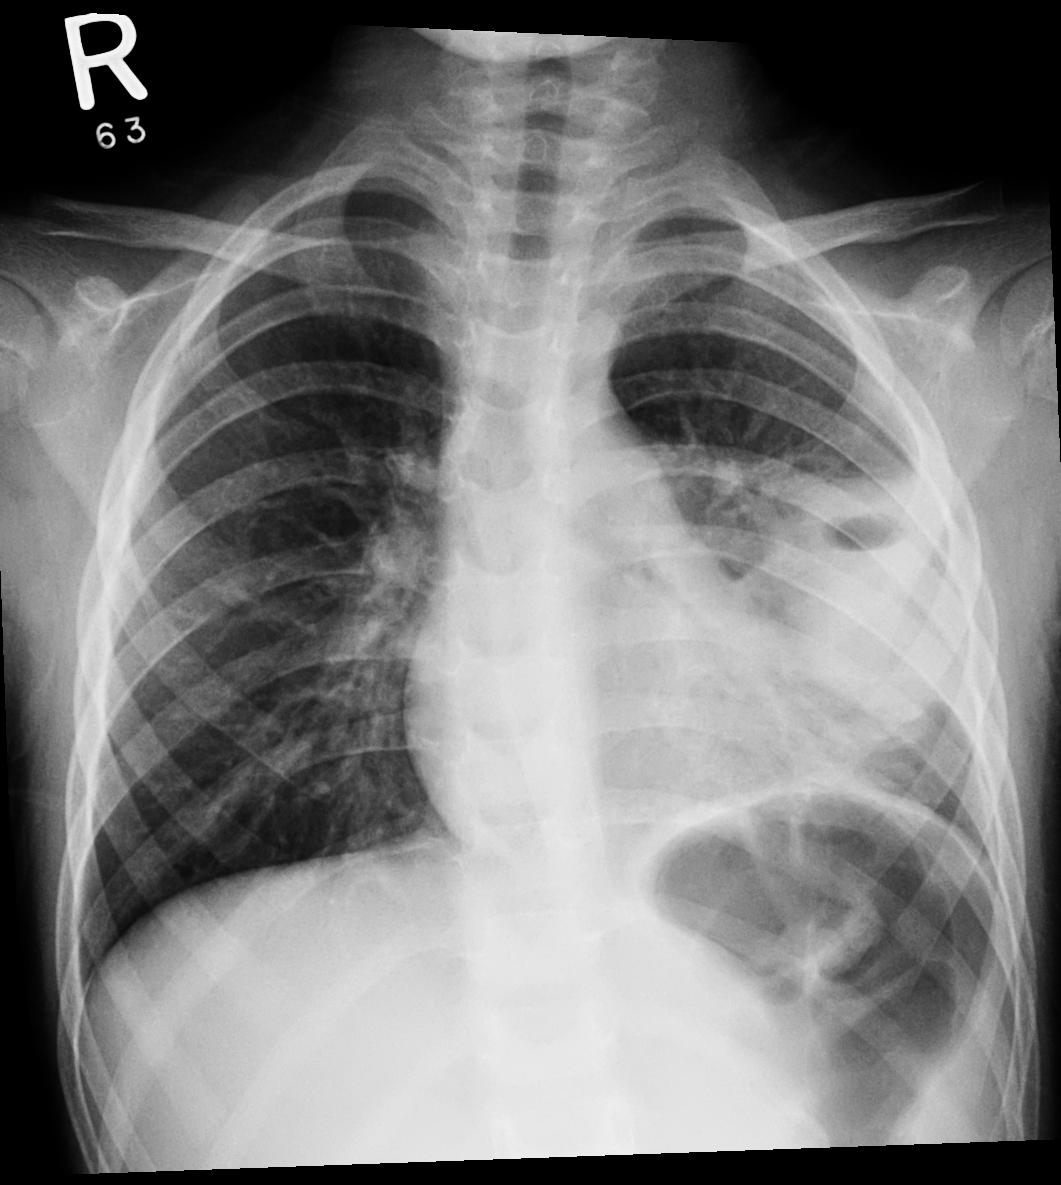

Chest Xray

Lung collapse/atelactasis

lung collapse

pneumonia

Lung abscess in left lung middle zone

Left lobar pnaeumonia

Left lower lobe homogenous opacity

Lft pleural effusion

left lung abscess, tracheal deviation

Absces